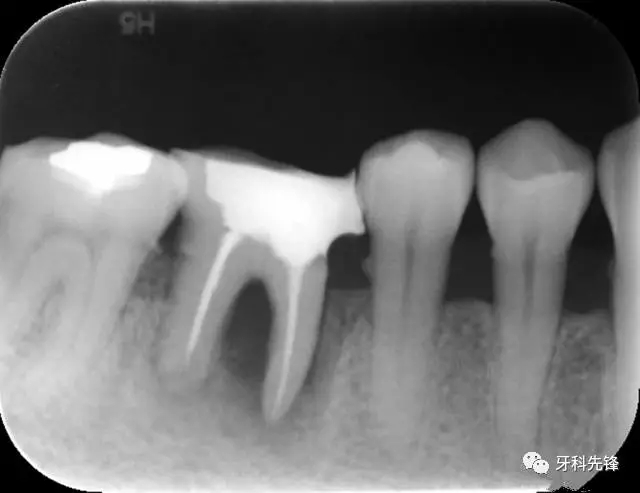

圖1 術(shù)前X光片

圖8治療術(shù)后X光片